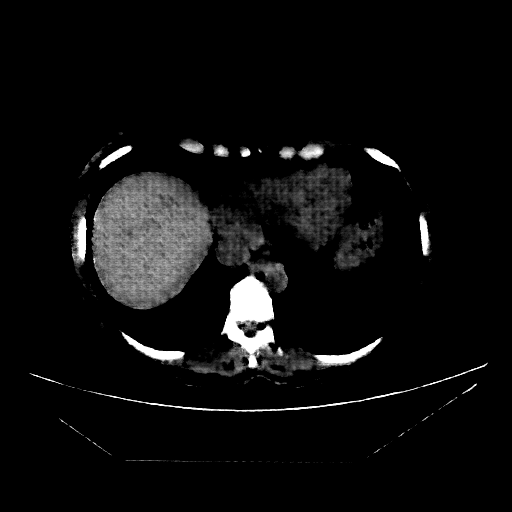

Image Grid

4Γ—3 grid: Rows show different image types (Original NATIVE, Reconstructed NATIVE, Original VENOUS, Generated VENOUS), Columns show windowing techniques (No Window, Lung Window, Mediastinum Window)

Generated VENOUS CT scan (A→B translation)

Full window (WL 1023.5, WW 4095 β†’ Low βˆ’1024, High +3071)

Actual HU range: [-811.5, 753.5]

Lung window (WL -600, WW 1500 β†’ Low βˆ’1350, High +150)

Actual HU range: [-811.5, 150.0]

Mediastinum window (WL 40, WW 400 β†’ Low βˆ’160, High +240)

Actual HU range: [-160.0, 240.0]